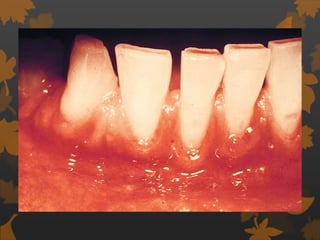

Effect on gingiva

 Tendency towards enlarged gingiva,

sessile/ pedunculated gingival polyp,

polypoid gingival proliferation, abcess,

periodontitis , mobility of teeth.

Hirschfeld I, 1934

PERIODONTAL MANIFESTATIONS

 Tendency towards enlarged gingiva.

 Sessile/pedunculated gingival polyps.

 Polypoid gingival proliferations

 Abscess formation

 Periodontitis

 Loosened teeth - Hirchfeld I (1934)

GINGIVITIS

 Diabetes is associated with increased

prevalence and severity of gingivitis.

 Children before puberty with poorly controlled